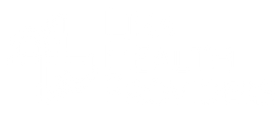

Órganos internos: corazón, pulmones, hígado, riñones, sistema digestivo y reproductivo.

3B Scientific

Cerebro de Lujo con Arterias, desmontable en 9 piezas - 3B Smart Anatomy

Precio de venta$18,177.53